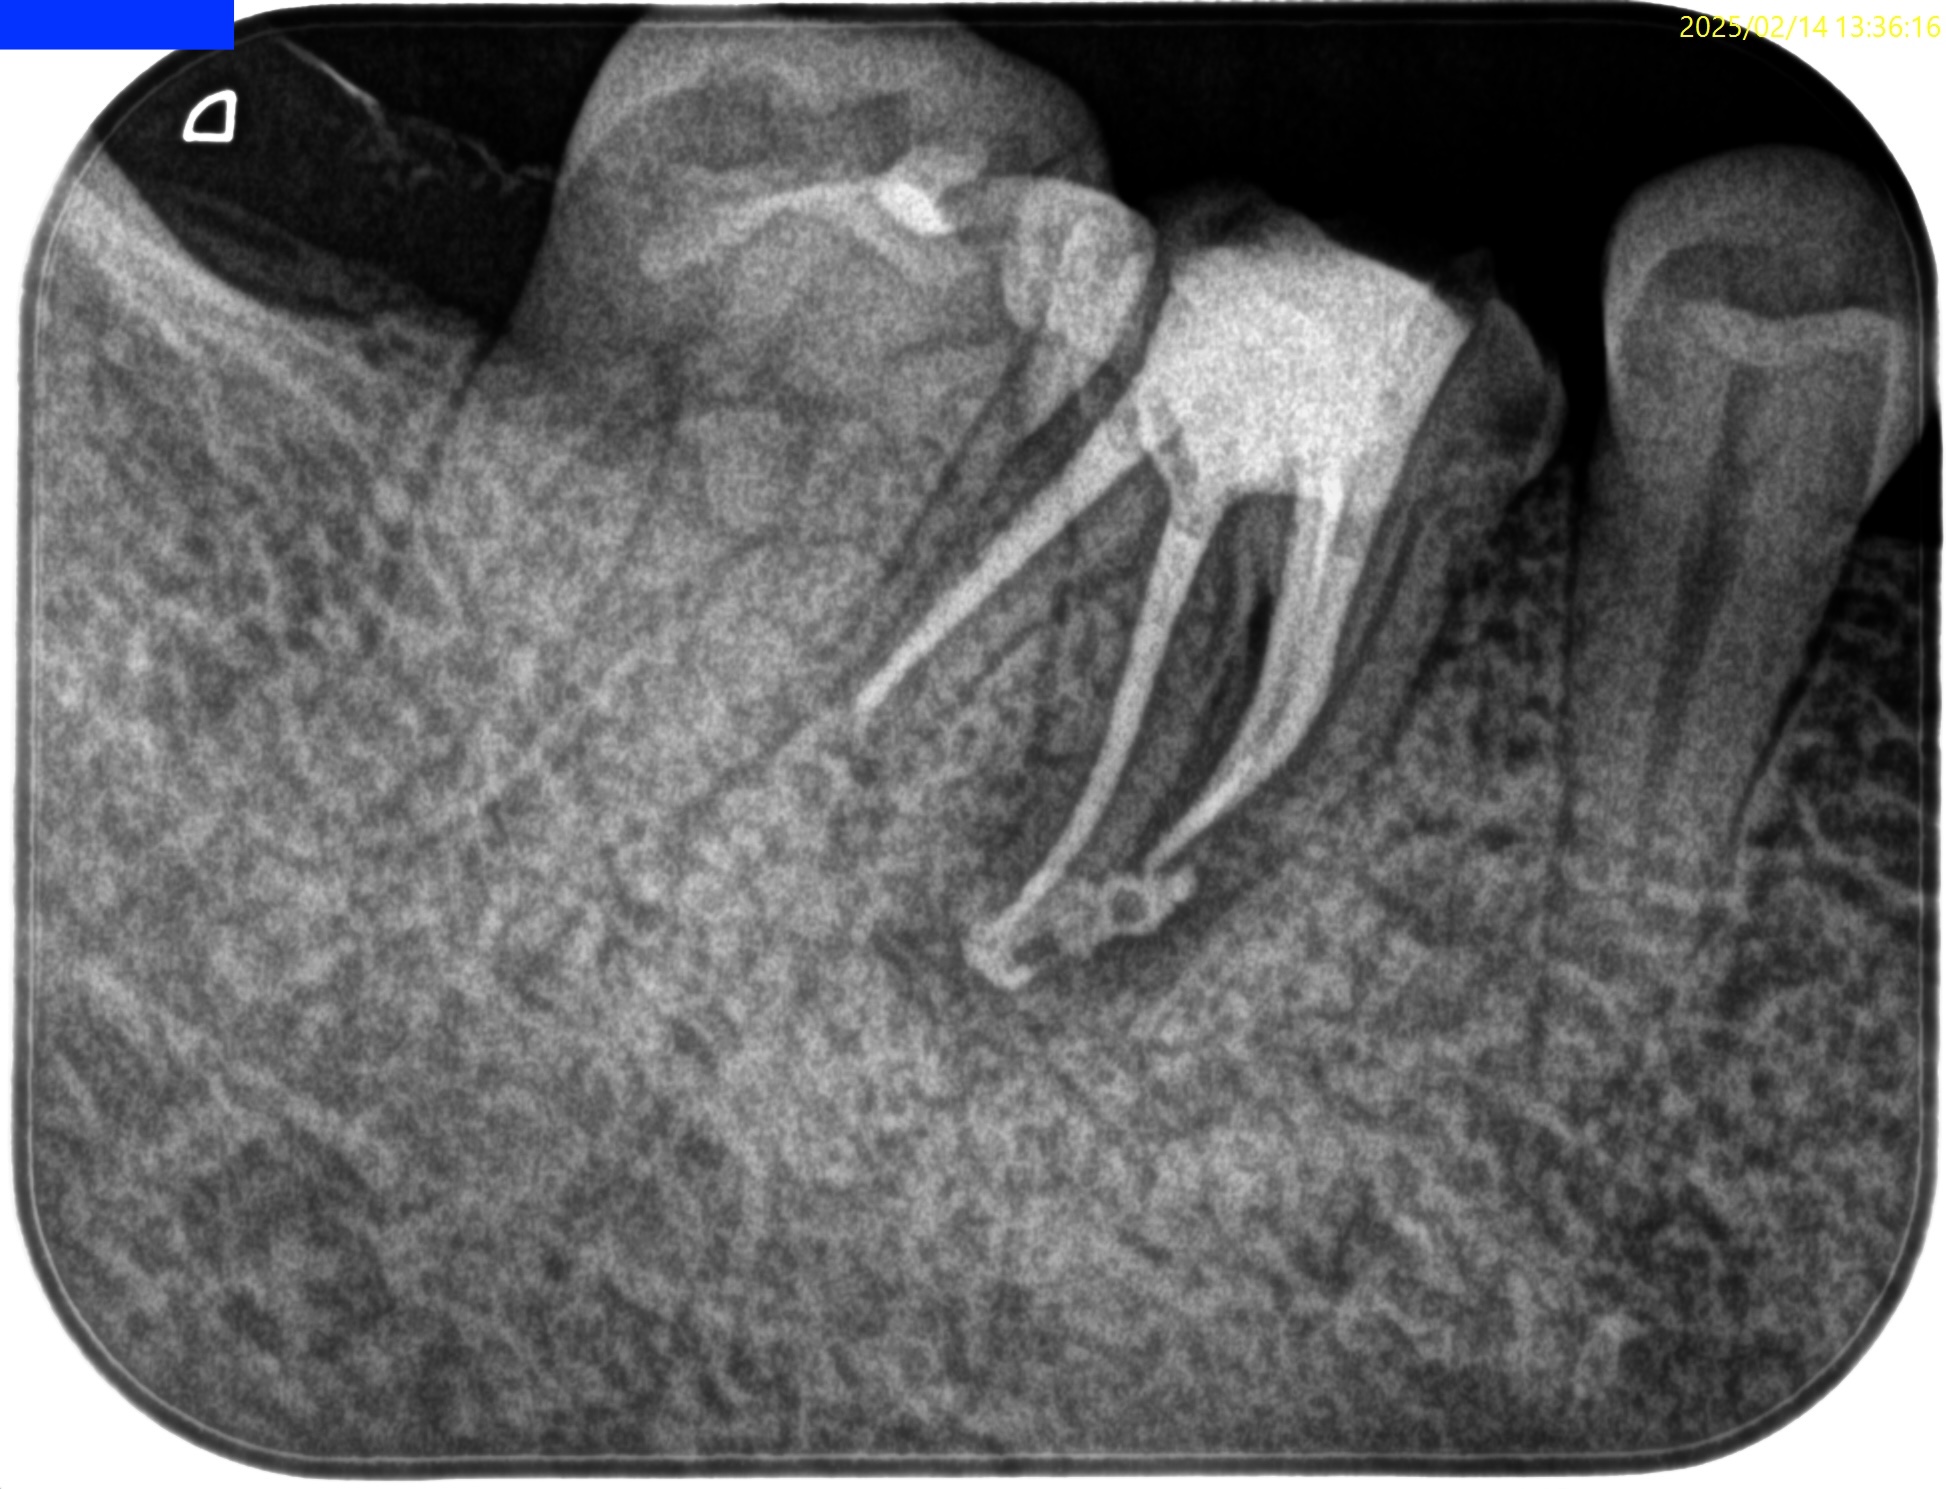

Pre-op Endo test(2025.2.14)

MB

ML

D

Radix

そこそこ湾曲度合いが強いRadix Entomolarisを有する#30だ。

が、D以外の根管はほぼ適切な根管治療がなされていない。

Radixにおいては未着手だ。

Pre-op Endo diagnosis(2025.2.14)

Pulp Dx: Previously treated

Periapical Dx: Symptomatic apical periodontitis

Recommended Tx: Re-RCT